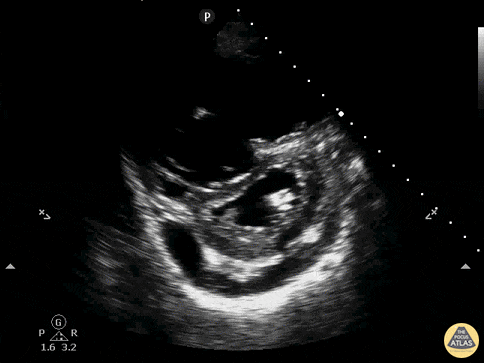

Right Ventricular Dysfunction - D-Sign with RV Dilation, Effusion, PSSA

A patient presenting with acute onset undifferentiated shortness of breath. POCUS was used to narrow the differential. Parasternal short axis demonstrated flattening of the interventricular septum which pushes the left ventricle into the shape of the letter D. Known as the sonographic D-sign, it is correlated with significant right ventricular overload. This sign is not highly sensitive for PE, but can be 80-90% specific when found and associated with other signs of right ventricular strain. Also note on this study: moderate pericardial effusion, right ventricular dilation. Drs. Ronald Rivera, Elizabeth Hanson, Melanie Malloy, Kelly Maurelus, Kings County/SUNY Downstate Emergency Medicine